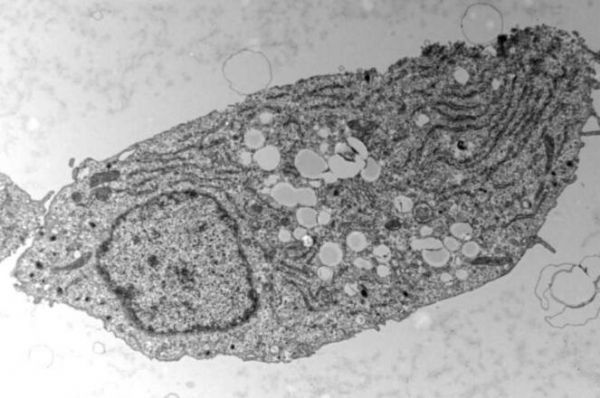

在一项新的研究中,来自德国科隆大学和马克斯普朗克生物老龄化研究所等研究机构的研究人员推断,微生物感染可以作为研究细胞对天然线粒体外膜应激作出反应的模型。为此,他们选择了人类寄生虫弓形虫,因为它将宿主线粒体与它自身的寄生虫空泡捆绑在一起;在被感染的细胞中,宿主线粒体外膜与寄生虫空泡膜之间形成了紧密的膜贴合区域。